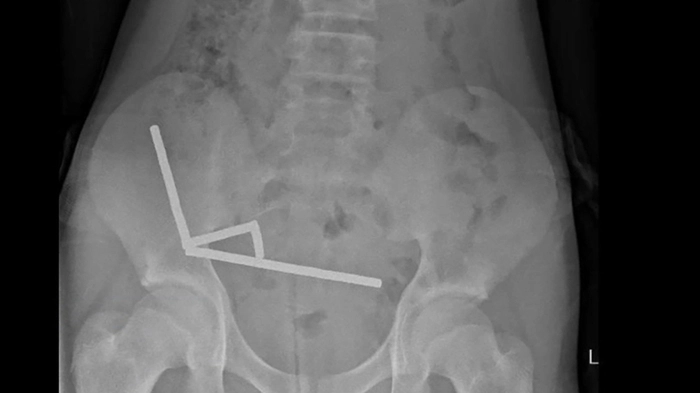

Chirurgen in Neuseeland haben dutzende Magneten aus den Gedärmen eines 13 Jahre alten Buben entfernt. Der Bub habe bis zu 100 Hochleistungsmagneten heruntergeschluckt, die er zuvor beim Billig-Onlinehändler Temu bestellt hatte, teilten die Ärzte am Freitag mit. Der 13-Jährige habe vier Tage lang unter Unterleibsschmerzen gelitten, bevor er in das Tauranga-Krankenhaus auf der Nordinsel Neuseelands eingeliefert worden sei.

Die Magneten ordneten sich im Darm neu an | Die Magneten ordneten sich im Darm neu an

Die Magneten ordneten sich im Darm neu an